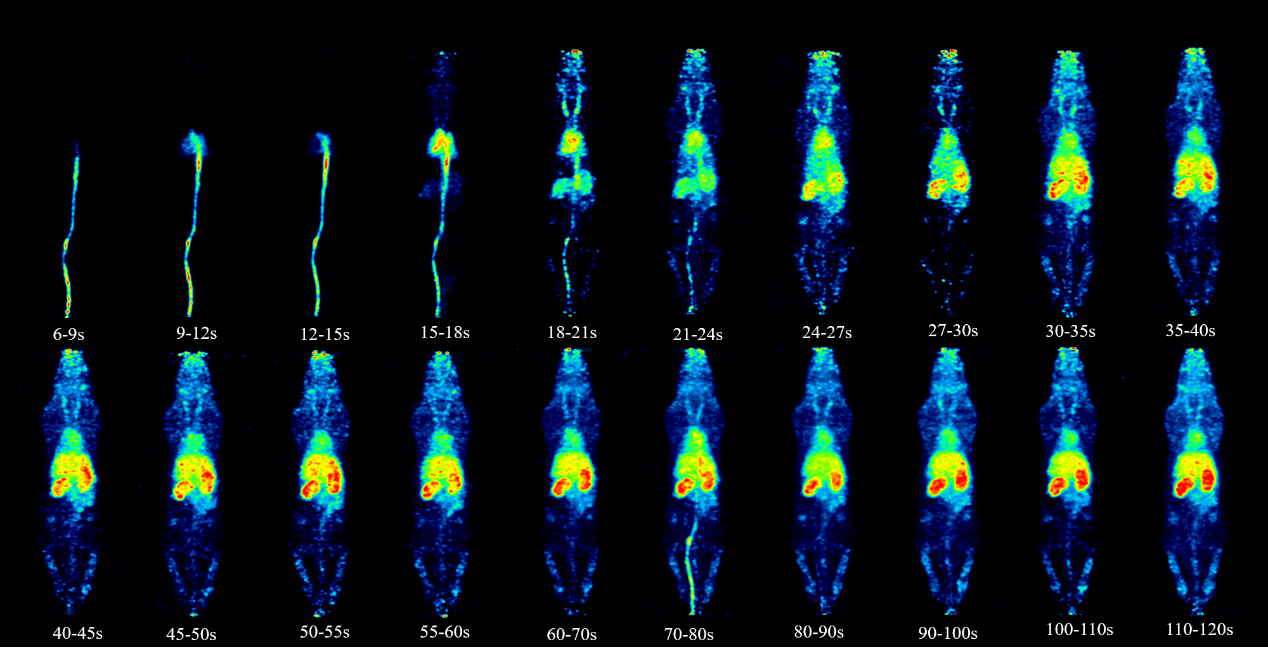

基于该设备成功实现了SD大鼠全身动态代谢成像(图2),成像结果清晰呈现了18F-FDG示踪剂从尾静脉注射后,经心脏循环至肝肾代谢的全过程,在单台设备上经单次扫描完成了大鼠多器官药代动力学连续监测。该技术突破为多靶点示踪成像、肿瘤转移机制研究及新药疗效评估提供了高精度研究平台,相关技术已申请国家发明专利3项。

图2 大鼠全身动态成像结果